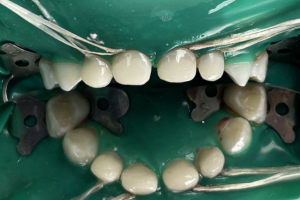

Семейная областная стоматология "Кидди Дентал" - это команда компетентных врачей, каждый из которых знает и любит свое дело. Опыт наших врачей, использование современного оборудования и надежных материалов позволят проводить лечение любой сложности.